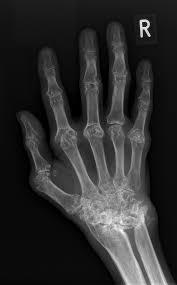

Arthritis: A clinico-imaging case-based multi-modality approach

Coordinators

Dr. Vineeth Joseph Abraham

Dr. Benjamin Barsouma Mathew

Dr. Joseph KT